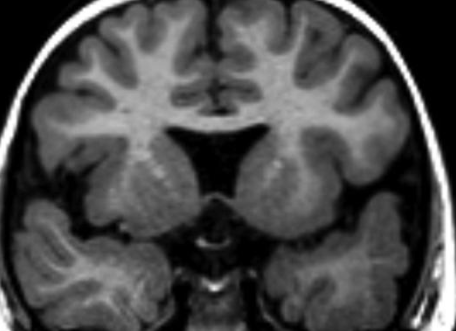

- Absence de Septum pellucidum

- Hypoplasie du chiasma optique

- Associée à la schizencéphalie ++